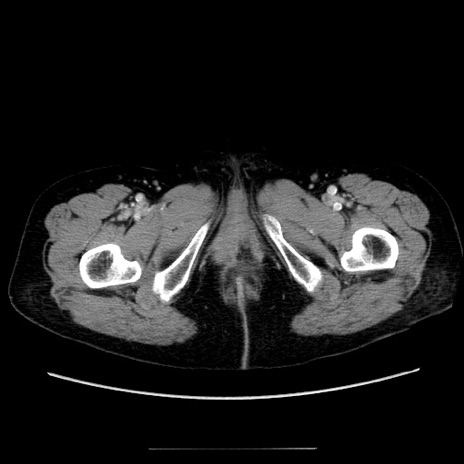

症例5(横断像)

【症例】70歳代女性

【主訴】お腹が張る

【現病歴】1週間くらい前から腹部膨満の自覚あり。昨日夜から増悪したため、本日救急外来受診。

【身体所見】意識清明、BT 36.5℃、BP 165/106mmHg、HR 80bpm、SpO2 98%、腹部:膨満、軟、自発痛・圧痛なし、触診にて不快感あり、腸蠕動音:減弱

【データ】WBC 12600、CRP 1.04